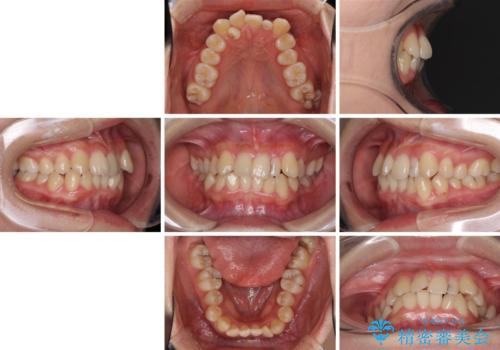

八重歯の抜歯矯正 補助装置を用いたインビザライン矯正

- 上顎の重なっている前歯を気にして来院された患者様です。

重なっている部分は抜歯が必要で、歯の移動量が多く、更には右側にずれている正中を改善する必要がありました。

インビザライン単体での治療は困難と判断し、補助装置により八重歯移動後にインビザラインを用いることとしました。

非常にしっかりとマウスピースを装着してくださいましたが、前歯の排列がなかなか仕上がらずに期間がかかってしまいました。